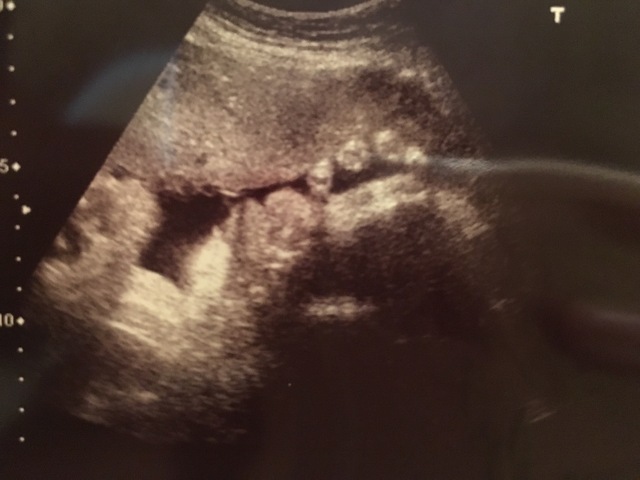

34週3日(34w3d・男の子)|ほー さん(27歳)

エコー写真撮影時のエピソード:

エコーのときに初めて指すいを見ることができました。いつもお腹をポコポコ蹴っていて元気な子やなと思っていましたが、エコーのときは静かになって指すいをしている姿を見て、とても赤ちゃんという感じを目の当たりにできすごく嬉しかったです。看護婦さんにも珍しい!かわいい!といわれ、終始にやにやと診察を受けました。